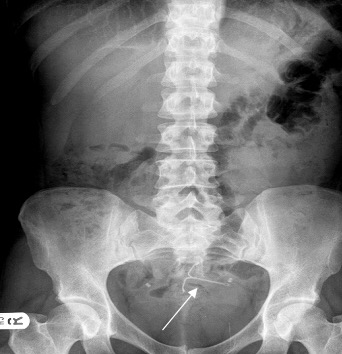

A non-hormonal contraceptive option offered to females is the copper intra-uterine device (IUD).

This device is implanted into the wall of the uterus, in an attempt to trick the body into believing an ovum has already attached to the endometrial lining. If the body senses implantation, then them it tricks the system into thinking its pregnant.